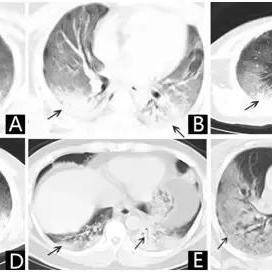

新冠肺炎的世界排名,新冠肺炎世界排位

新冠肺炎全球范围内爆发,其世界排名根据疫情严重程度、感染人数、死亡人数等指标不断变化,新冠肺炎在全球疫情中仍占据重要位置,世界各国都在积极应对,关于其具体世界排位,需参考最新数据和权威机构的报告。新冠肺炎的世界排名及...

今日疫情新闻哈尔滨最新,今日疫情最新消息数据哈尔滨

哈尔滨最新疫情新闻摘要:根据最新消息,哈尔滨市今日疫情数据有所更新,当地正在密切关注疫情动态,并采取一系列措施进行防控,具体数据尚在统计中,请关注官方发布的最新消息以获取准确信息。哈尔滨最新动态随着全球新冠疫情的...